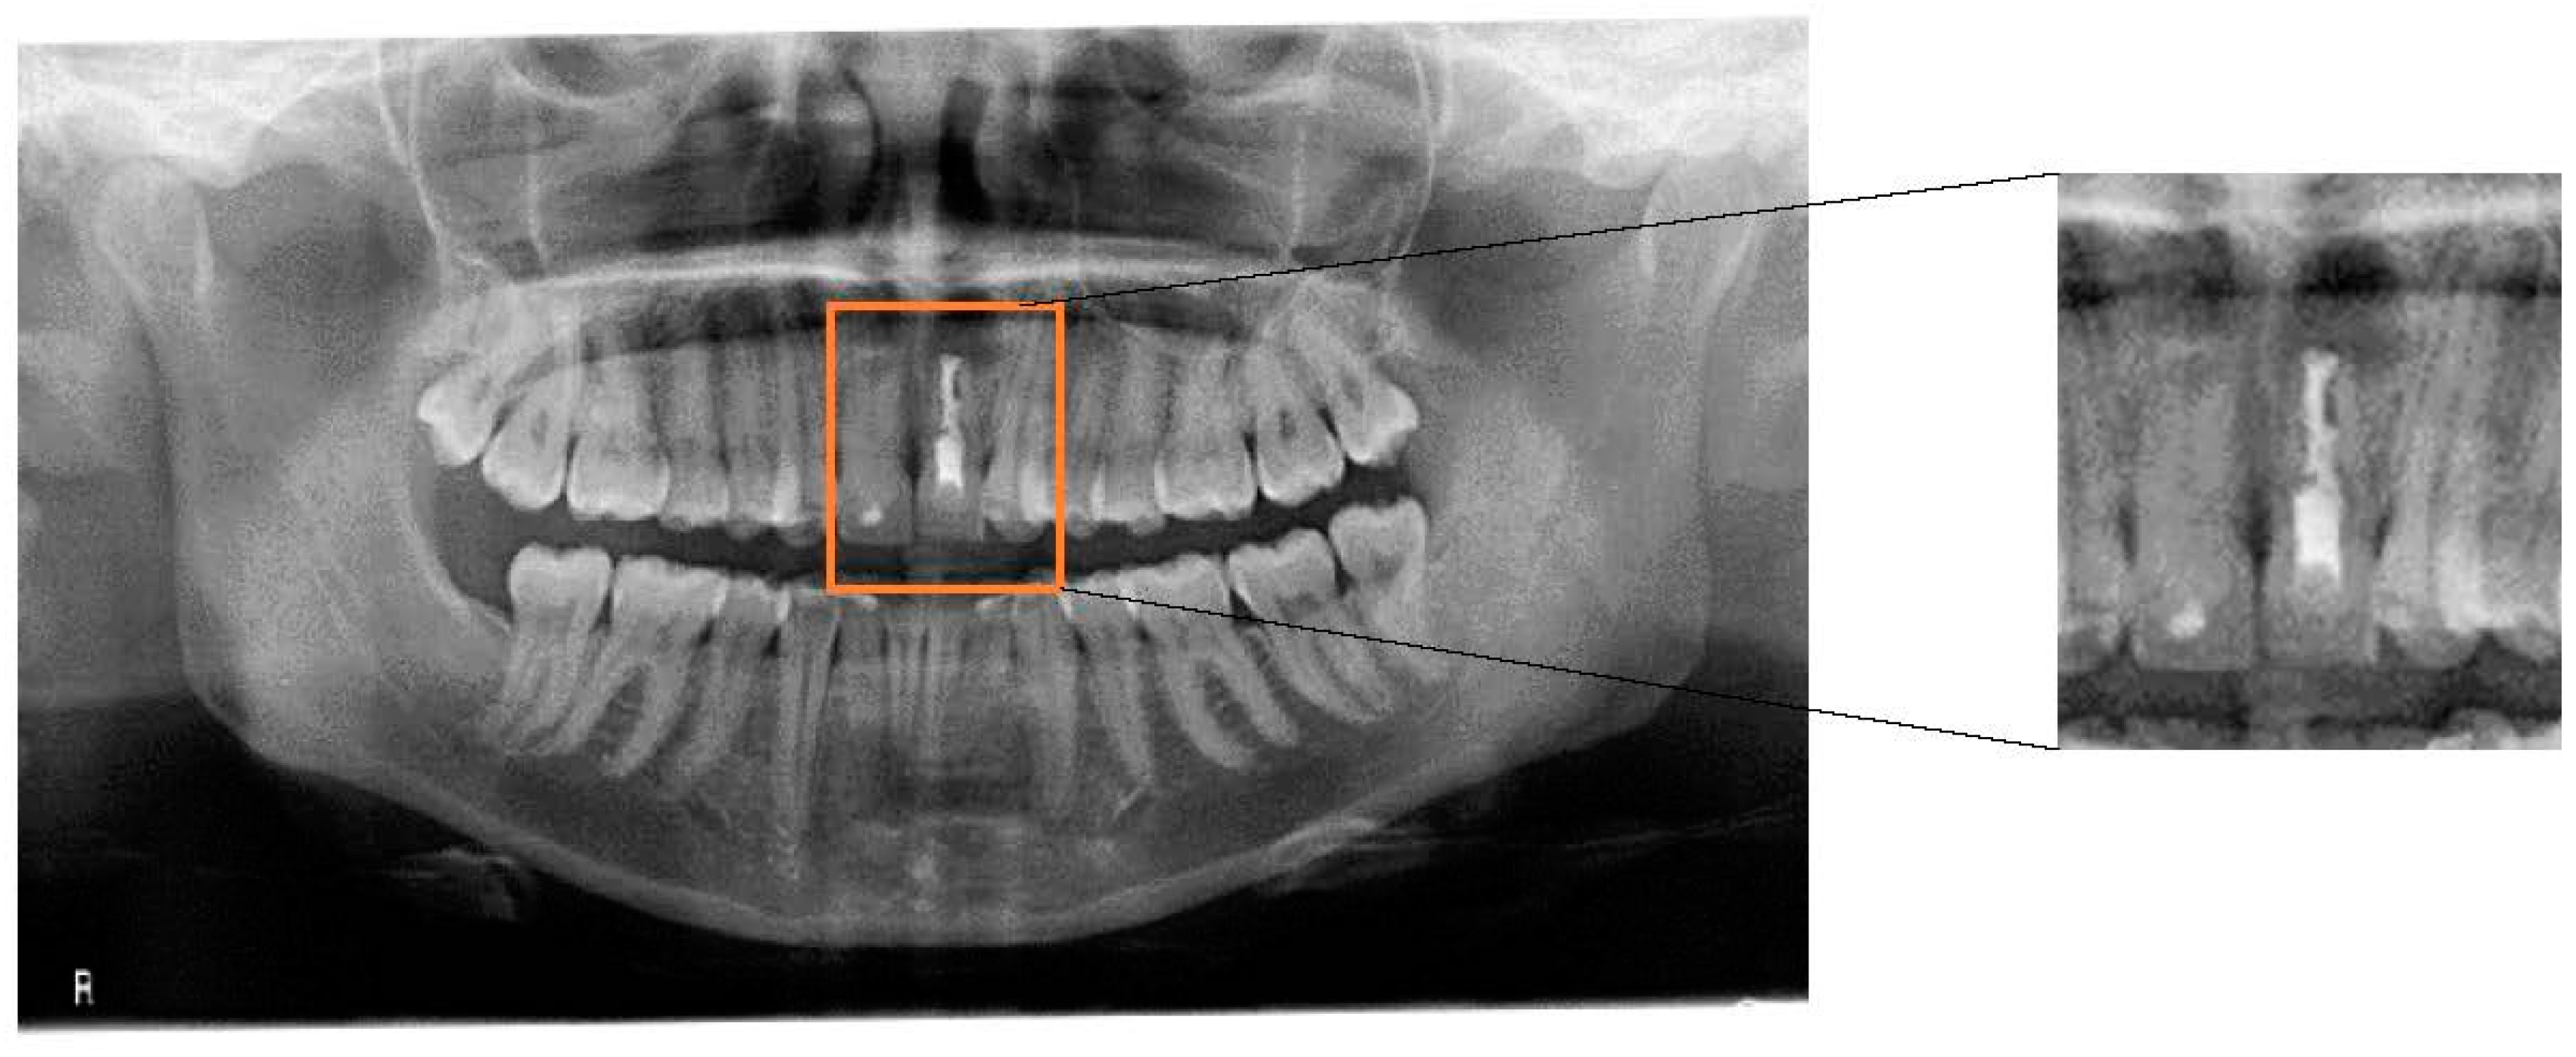

This case report is of a female professional saxophone player. The collection of information on the patient’s general health was performed prior to the clinical examination. The musician underwent a radiographic examination which consisted of the acquisition of a panoramic X-ray (Figure 1). Subsequently, two piezoresistive sensors (FlexiForce™, Tekscan, Boston, MA, USA, 0.07 kgf/cm2) were placed on the upper surface of the mouthpiece in order to quantify the pressure applied to the central incisors during the embouchure. In order to understand the values involved during this procedure, it was requested that the saxophone player perform three different notes at different pitches: high, medium, and low. This procedure was repeated three times for each pitch in order to obtain a medium value for each note. The sensors were previously calibrated and integrated with the recommended circuit from Tekscan and connected to a four-channel Universal Analog Input Module 9219 mounted in a NI-USB 9162 Carrier (National Instruments, Austin, TX, USA). To achieve the recommended circuit, a TL074 STMicroelectonics operational amplifier was used. Sensor characterization was made through polynomial regression. In this way, four different weights (100 g, 250 g, 500 g and 1000 g) were applied to the sensors and the voltage output was observed with a LabVIEW 2011 Carrier (National instruments, Austin, TX, USA). The FlexiForce Model A201-1 lb/sqi “TekScan” sensors were applied at specific locations on the mouthpiece as seen in Figure 2, where there is the usual tooth pressure.

Figure 1.

Panoramic radiograph of the patient. A radiolucid periapical lesion on tooth 21 can be observed, which did not disappear after endodontic treatment and apicoectomy.